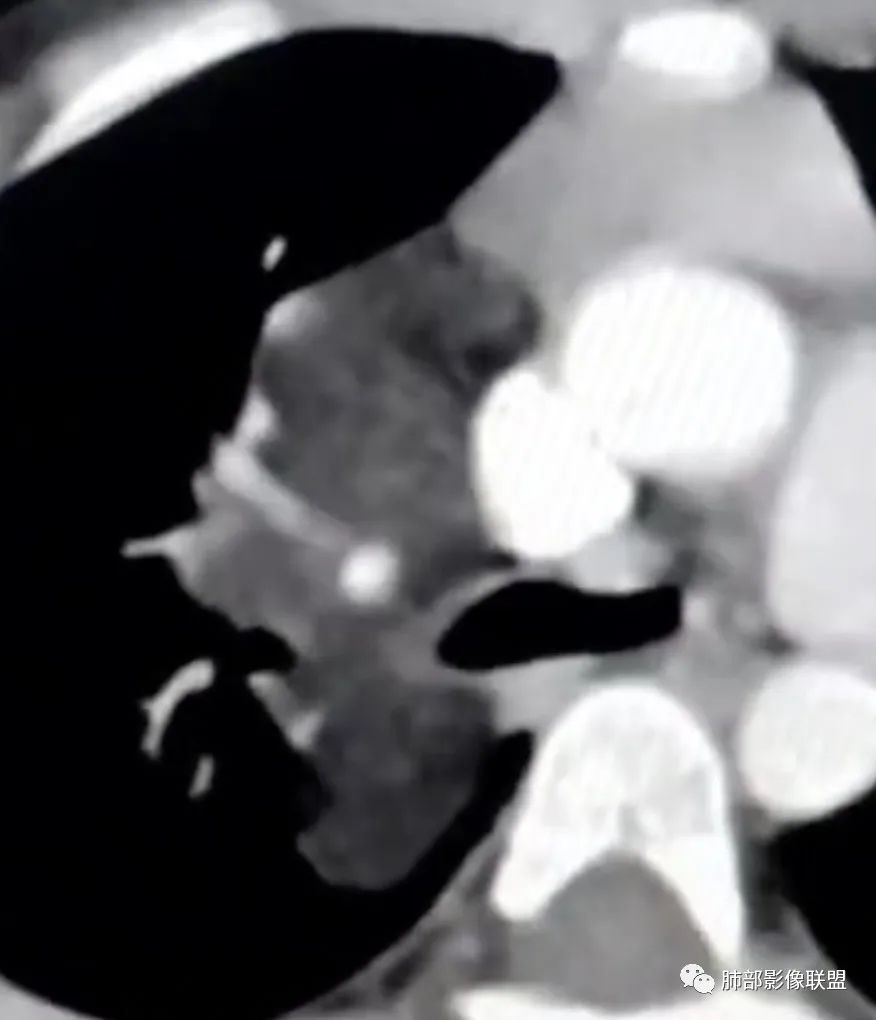

可以看到造影剂进入的丛状结构

密度不均,非纯脂肪成分。斑片状密度略高区域有轻度填充式强化。

婴幼儿,病变较大,跨肺门,分叶,富含纤维或黏液、含成熟脂肪,破坏力弱或无,浸润性生长模式不明显,未见远处转移。

综合:富含成熟脂肪的、可以有丛状结构的,可以有纤维或黏液的良性或低度恶性肿瘤。常见疾病谱:脂肪瘤、神经纤维瘤样错构瘤、冬眠瘤、血管脂肪瘤、髓脂肪瘤、脂肪母细胞瘤、黏液样脂肪肉瘤。